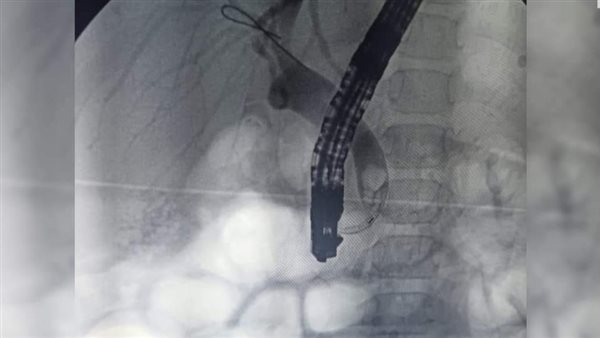

وأشار "شعبان"، إلى أنه تم عمل الفحوصات اللازمة وتبين إصابتها بارتفاع شديد بنسبة الصفراء في الدم وأنيميا حادة، كما تم عمل أشعة رنين مغناطيسي على القنوات المرارية، والتي أظهرت انسدادًا حصويًّا بالقنوات المرارية، وكيسًا صفراويًّا، وتم كذلك عمل منظار للقنوات المرارية، واستخراج الحصوات وتركيب دعامة بلاستيكية لتأمين عدم تكرار الانسداد مرة أخرى، وتم نقل الطفلة لمستشفى النصر التخصصي للأطفال بعد الاطمئنان عليها لاستكمال العلاج والمتابعة.